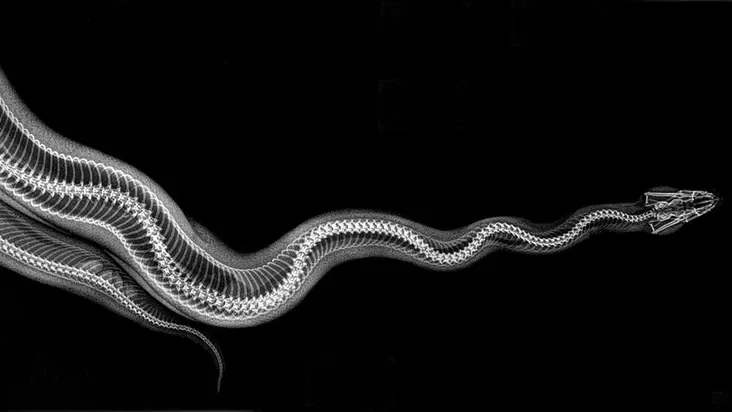

Зоопарк в американском штате Орегон опубликовал рентгеновские снимки своих животных. Их сделали во время медосмотра.

По словам представителей зоопарка, рентген — один из самых эффективных методов диагностики у животных. Кроме того, он позволяет минимизировать время анестезии при операциях.

Такие снимки редко обнародуют, поскольку их делают исключительно в исследовательских целях.

Королевский питон.